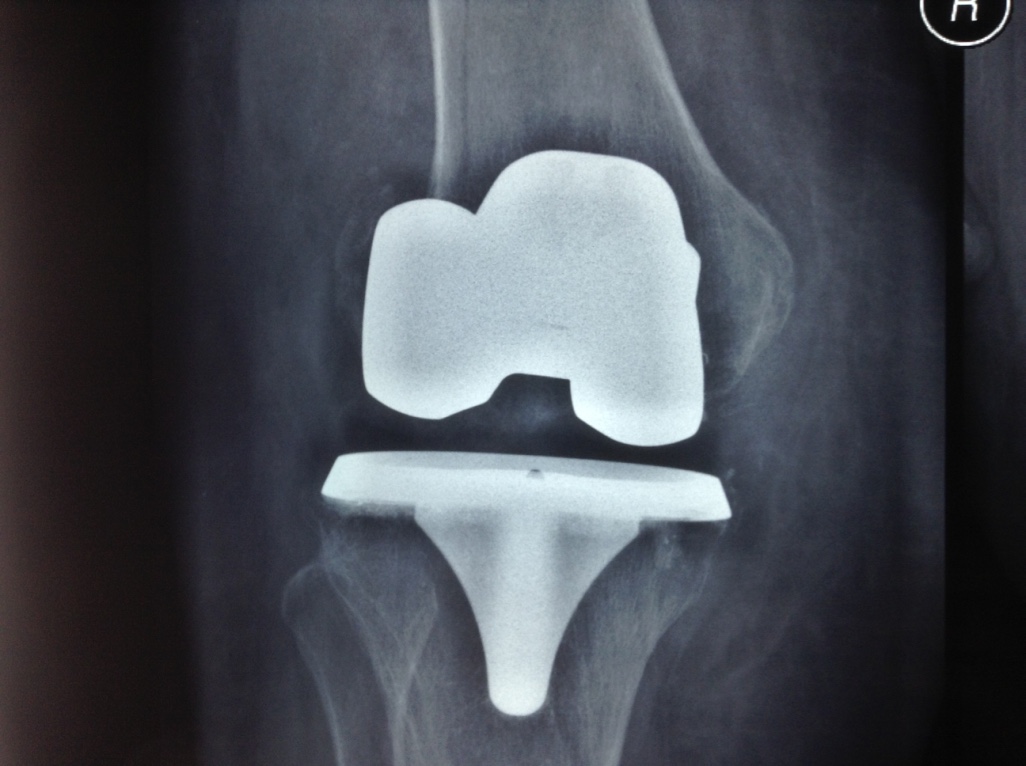

Revision Total Knee Replacement After a fructure

• Revision Total Knee Replacement After a fructure